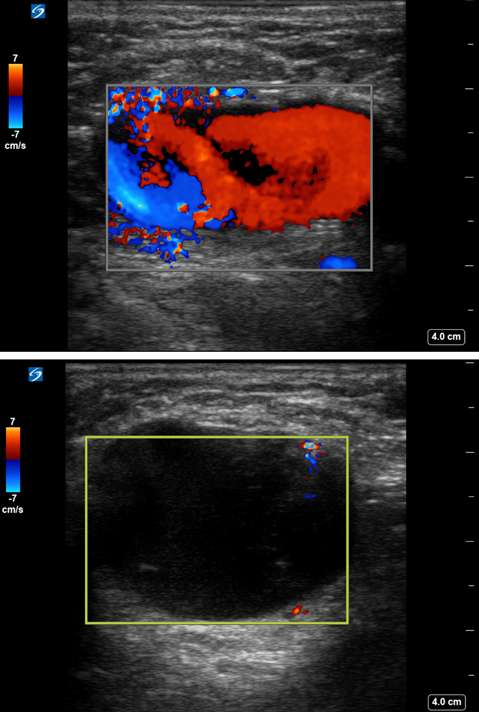

Arteriovenous malformations of the breast are rare. Most cases of breast AVMs are acquired or iatrogenic, either secondary to trauma or following biopsy or surgery. Congenital breast AVMs of are an exceedingly rare clinical entity usually seen in association with other systemic vascular anomalies as part of a syndromic vascular malformation disorder. Initially, a breast AVM may be detected by screening mammography as a nonspecific focal asymmetry or mass, which may trigger subsequent diagnostic breast imaging. The diagnosis can be readily made by duplex ultrasonography as a high-flow complex vascular mass with one or more feeding vessels and a draining vein (Figure 4), with CT or MRI usually reserved for preoperative planning purposes or equivocal cases. Presence of slow or no Doppler flow is more likely to represent a venous/venolymphatic malformation or primary vascular tumor rather than AVM. Treatment is achieved either by endovascular or surgical means. However, there is a paucity of literature on the appropriate management, and no guideline currently exists as the gold standard of care. Therefore, patients with breast AVMs should be evaluated by a multidisciplinary team at a center with a dedicated vascular malformations practice.